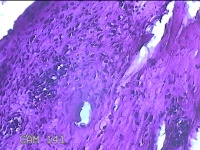

左侧膝部皮下结节

性别

男

年龄

7岁

临床诊断

皮下结节

一般病史

发现左侧膝部皮下结节2年余,无明显疼痛及不适。

标本名称

大体所见

灰白暗红色组织1.5x0.8x0.7cm一块,表面带梭形皮肤1.5x0.8cm,皮下见结节1.5x0.8x0.3cm一个,切开结节呈囊性,囊内有少许清亮液体,囊壁厚0.1cm。